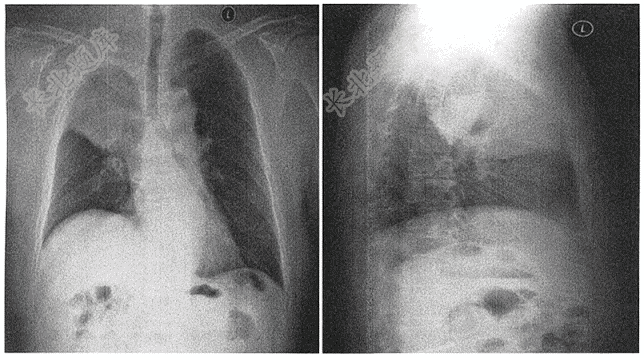

- 单项选择题男,62岁,咳嗽、咳痰,痰中带血1周( )

D、中央型肺癌